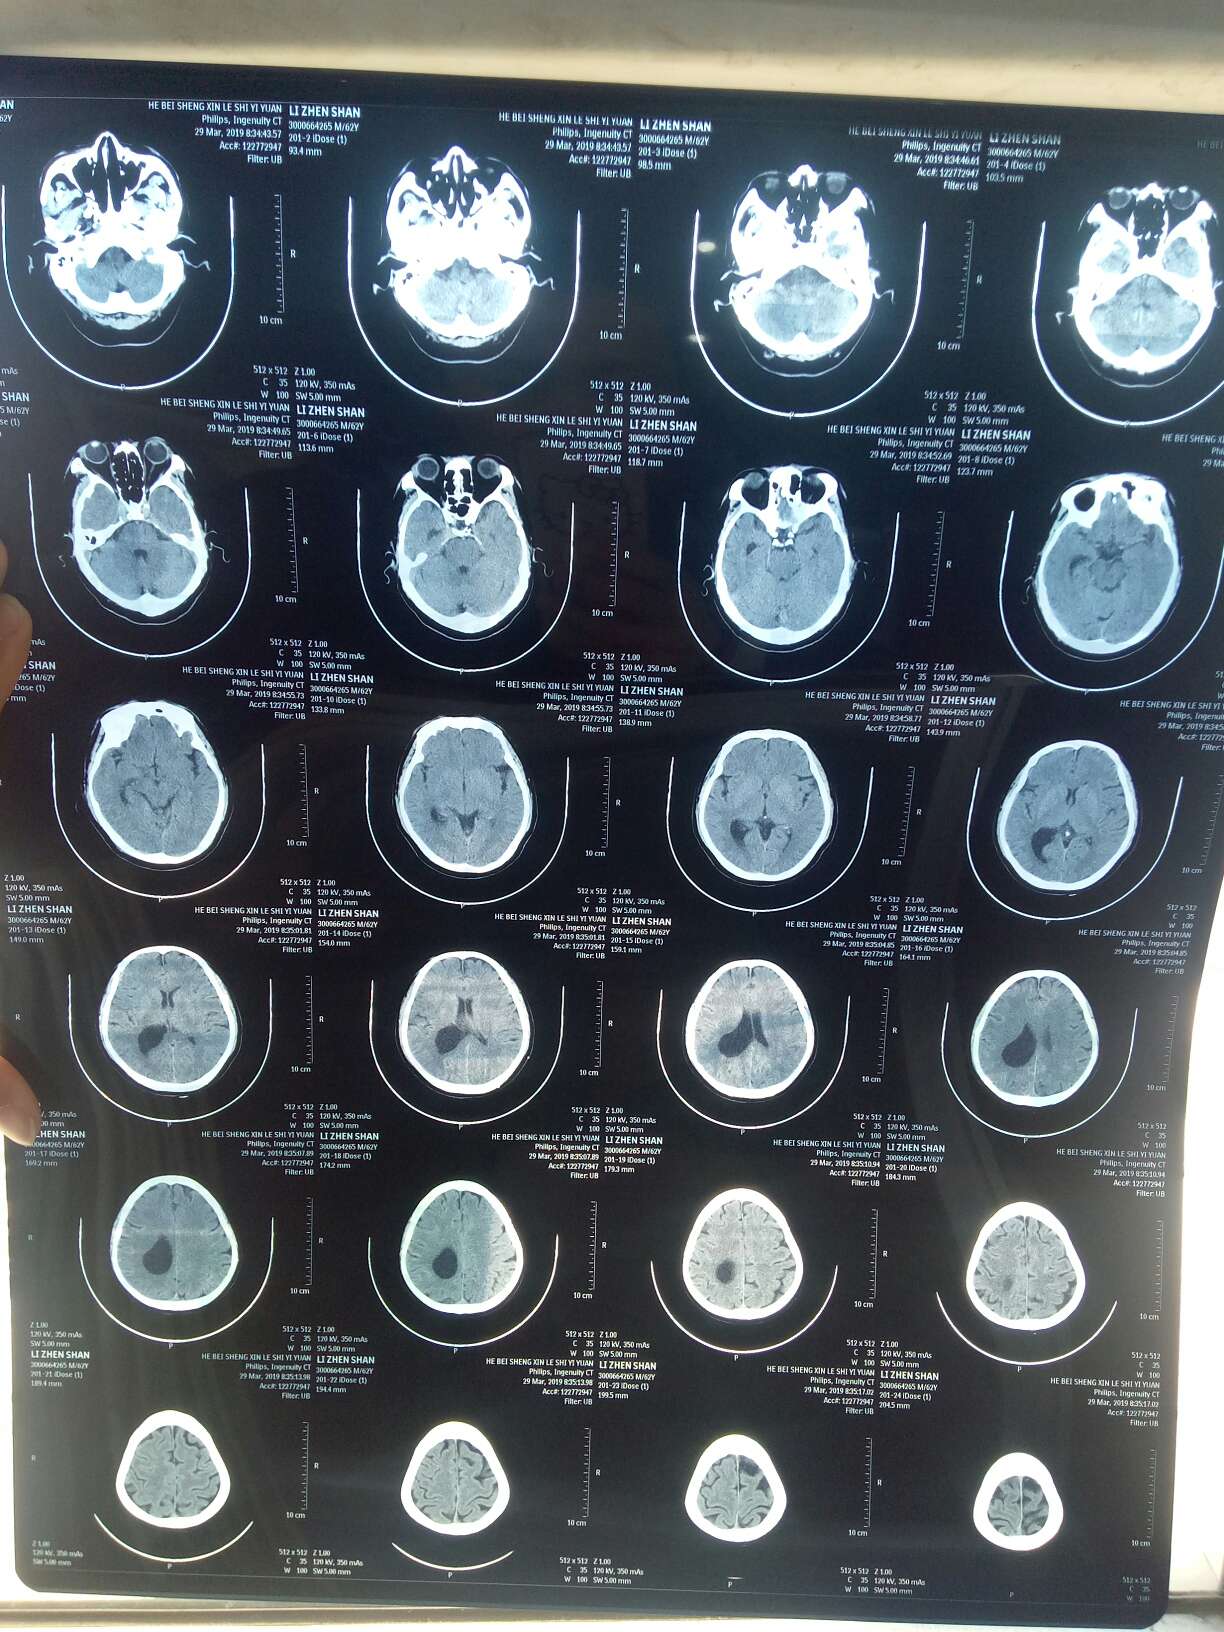

3月29日CEA继续下降至14.8。同时做了头颅及全腹CT,原发灶缩小,小结节缩小或消失,胸膜增厚情况缓解。但此时胸痛,声音嘶哑,陈医生判断胸痛恰恰是好转的表现,很可能是由于胸水减少,肺复张造成的。果然,几天后胸口不痛了。